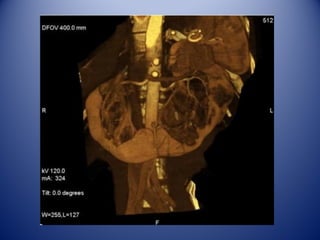

Parte posterior: 11 y 12 costillas.

• Por su cara posterior ambos riñones están en

contacto con el diafragma, el psoas mayor y

cuadrado lumbar